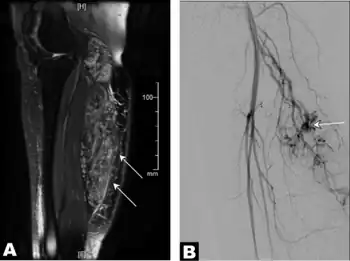

![]() | |

| a) Image with intravenous gadolinium contrast demonstrated an infiltrative vascular malformation in right gastrocnemius b) digital subtraction angiogram of right leg in a lateral projection during the arterial phase revealed arteriovenous shunting | |